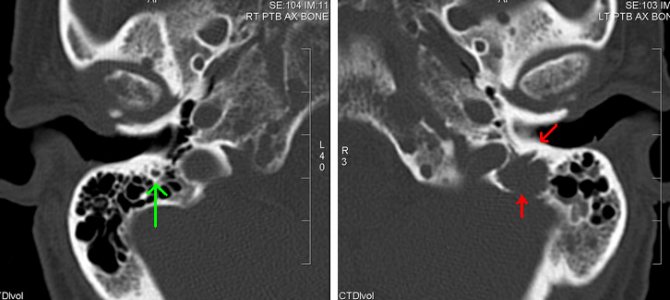

Рентгенологическая картина

Рентгеновская картина характеризуется большой вариабильностью. На типическом рентгеновском снимке определяются множественные очаги костной деструкции. Густые ограниченные деструктивные очаги сливаются с менее ограниченными и слабо выраженными просветлениями. Чередование остеолиза с пятнистыми сгущениями костной структуры создают своеобразную рентгенологическую картину множественной миеломы.

В стадии полного развития заболевания довольно часто выражена особая псевдокистозная структура, в особенности на черепе, ребрах, крыле подвздошной кости и позвонках.

- рентгенография грудной клетки и скелета для определения числа опухолей в кости;